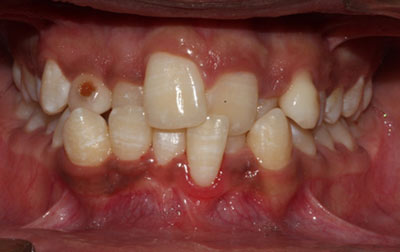

Children dentistry under general anesthesia (GA)- The utilization of general anesthesia (GA) can become necessary when dealing with young children undergoing dental procedures or teenagers who experience anxiety in the dental chair. Ensuring proper dental care for children holds immense significance, as any negligence can potentially result in serious future complications. In pediatric dentistry, the administration of general anesthesia (GA) serves the purpose of inducing a state of complete sleep in the child, ensuring their full cooperation with the pediatric dentist, and eliminating any pain sensations. This anesthesia is skillfully administered by a specialized medical professional known as an anesthesiologist. Throughout the entire dental procedure, the anesthesiologist remains in close attendance, diligently monitoring the child's condition.

Following the dental treatment, the anesthesiologist takes on the responsibility of gently rousing the child from the anesthesia-induced sleep, prioritizing their comfort and tranquility. This comprehensive approach helps to guarantee a positive and stress-free dental experience for both children and individuals who may be apprehensive about dental treatments.